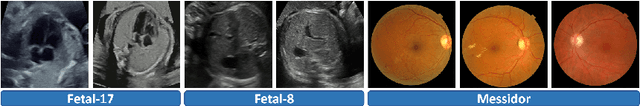

Abstract:Fetal pose estimation in 3D ultrasound (US) involves identifying a set of associated fetal anatomical landmarks. Its primary objective is to provide comprehensive information about the fetus through landmark connections, thus benefiting various critical applications, such as biometric measurements, plane localization, and fetal movement monitoring. However, accurately estimating the 3D fetal pose in US volume has several challenges, including poor image quality, limited GPU memory for tackling high dimensional data, symmetrical or ambiguous anatomical structures, and considerable variations in fetal poses. In this study, we propose a novel 3D fetal pose estimation framework (called FetusMapV2) to overcome the above challenges. Our contribution is three-fold. First, we propose a heuristic scheme that explores the complementary network structure-unconstrained and activation-unreserved GPU memory management approaches, which can enlarge the input image resolution for better results under limited GPU memory. Second, we design a novel Pair Loss to mitigate confusion caused by symmetrical and similar anatomical structures. It separates the hidden classification task from the landmark localization task and thus progressively eases model learning. Last, we propose a shape priors-based self-supervised learning by selecting the relatively stable landmarks to refine the pose online. Extensive experiments and diverse applications on a large-scale fetal US dataset including 1000 volumes with 22 landmarks per volume demonstrate that our method outperforms other strong competitors.

Abstract:Deep classifiers may encounter significant performance degradation when processing unseen testing data from varying centers, vendors, and protocols. Ensuring the robustness of deep models against these domain shifts is crucial for their widespread clinical application. In this study, we propose a novel approach called Fourier Test-time Adaptation (FTTA), which employs a dual-adaptation design to integrate input and model tuning, thereby jointly improving the model robustness. The main idea of FTTA is to build a reliable multi-level consistency measurement of paired inputs for achieving self-correction of prediction. Our contribution is two-fold. First, we encourage consistency in global features and local attention maps between the two transformed images of the same input. Here, the transformation refers to Fourier-based input adaptation, which can transfer one unseen image into source style to reduce the domain gap. Furthermore, we leverage style-interpolated images to enhance the global and local features with learnable parameters, which can smooth the consistency measurement and accelerate convergence. Second, we introduce a regularization technique that utilizes style interpolation consistency in the frequency space to encourage self-consistency in the logit space of the model output. This regularization provides strong self-supervised signals for robustness enhancement. FTTA was extensively validated on three large classification datasets with different modalities and organs. Experimental results show that FTTA is general and outperforms other strong state-of-the-art methods.